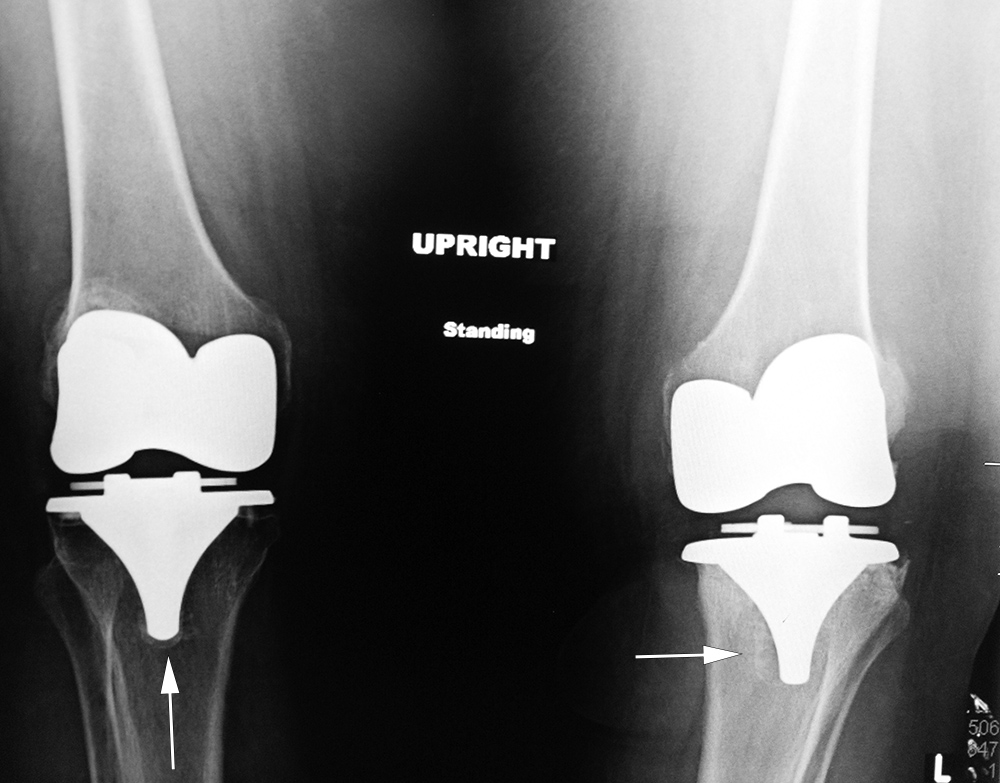

| 65 year-old woman with bilateral cruciate-retaining total knee arthroplasties (TKAs) placed in early 2009. In November 2015 routine follow-up showed bilateral aseptic loosening in both tibial components with wide periprosthetic lucencies (arrows) and varus deformity on the left. From left to right, respectively, AP radiograph of the right knee in the immediate postoperative period, AP radiograph of the right knee 6.5 years later, and standing frontal view of the knees 6.5 years after surgery. Images courtesy Laura H Lee, MD. |